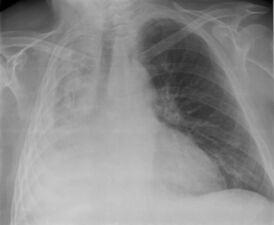

Достаточно часто у больных могут быть симптомы предшествующего поражения лёгких. При остро возникшем значительном ателектазе больные могут ощущать боль в грудной клетке, усиление одышки; при обследовании больного отмечают цианоз, некоторое отставание при дыхании поражённой половины грудной клетки, притупление перкуторного звука в соответствующем участке лёгкого, там же ослабление дыхания и голосового дрожания. Могут быть тахикардия, гипотония, при осложнении ателектаза инфекцией — повышение температуры. Однако часто при постепенном развитии ателектаза и небольших его размерах клинические симптомы могут быть выражены незначительно, и ателектаз диагностируется рентгенологически. При этом прозрачность поражённого участка лёгкого уменьшается, тень его часто имеет треугольную форму с верхушкой, обращённой в сторону корня лёгкого. При большом ателектазе может быть смещение органов средостения в поражённую сторону. Своеобразной формой ателектаза является так называемый синдром средней доли, обусловленный обтурацией крупного бронха увеличенным лимфатическим узлом. Чаще всего этот лимфатический узел оказывается поражённым вследствие перенесённого туберкулёза. Для уточнения причины ателектаза иногда приходится проводить томографию, бронхографию.

- Рентгенография органов грудной клетки, которая позволяет определить безвоздушный участок лёгкого.